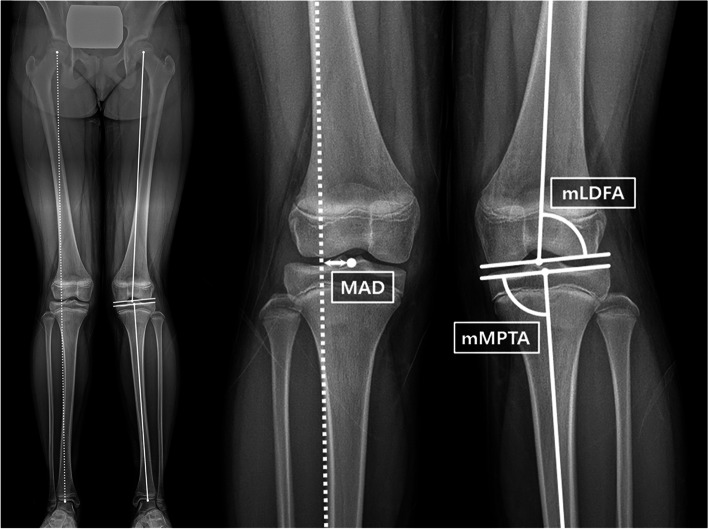

We measured mechanical axis deviation (MAD) and two mechanical angles (lateral distal femoral angle [mLDFA] and medial proximal tibial angle [mMPTA]) using standing anteroposterior full-leg radiographs with the patella facing forward taken at pre-corrective operation, pre-implant removal, and the final follow-up [19]. The MAD was defined as the distance from the midpoint of the tibial plateau to a line connecting the centers of the hip and ankle joint (Fig. 2). The mLDFA and mMPTA were measured using the mechanical axis of each bone and the corresponding joint line. The correction angle was defined as the difference between the implant insertion and the subsequent removal using the mechanical angle according to the target physis. The correction period refers to the time in months between first and second surgeries, and the correction rate was also calculated as the correction angle divided by the correction period.

Fig. 2.

Radiographic measurements of mechanical axis deviation (MAD), mechanical lateral distal femoral angle (mLDFA) and mechanical medial proximal tibial angle (mMPTA).